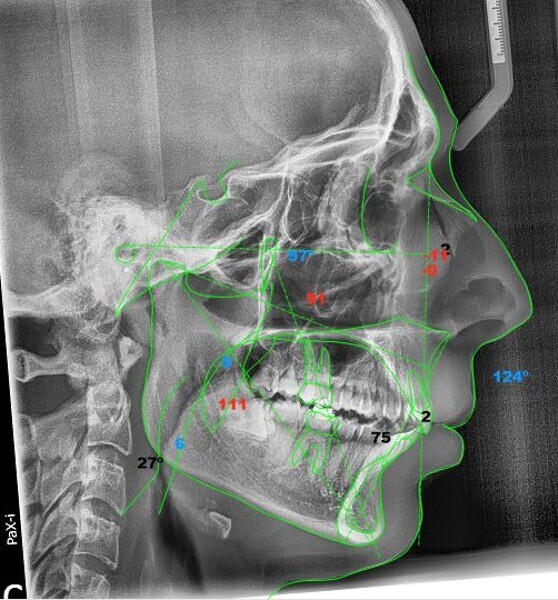

In the radiographic analysis, the dental panoramic tomogram revealed that the two mandibular third molars were unerupted and horizontalised in the mandible. Nothing else relevant was observed in the radiograph (Fig. 3). A cephalometric radiograph was used to perform the cephalometric analysis according to Steiner,6 Ricketts7, 8 and McNamara9 (NemoCeph Studio, Nemotec Fig. 4).

In the Steiner analysis, the SNB angle of 74° suggested mandibular retrusion. Likewise, the ANB angle of 7° indicated Class II, which was also confirmed by Wits analysis (8.3 mm). The results indicated a protrusion of the maxillary incisors and a decreased inter-incisal angle of 118°, which suggested protrusion of the maxillary and mandibular incisors (Fig. 5).

In the Ricketts analysis, a dolichofacial pattern, that is, a facial axis of 84°, was diagnosed. The analysis also confirmed the protrusion of the incisors (Fig. 6).

The McNamara analysis revealed that the size of the mandible that would correspond to the dimensions of the maxilla (91.0 mm) would be between 114.0 mm and 117.0 mm and not the current size of 111.9 mm,9 indicating that the mandible was smaller than it should have been. However, the maxillomandibular difference was 20.9 mm, indicating a Class II skeletal pattern (Fig. 7). From the aforementioned information, we determined a Class II skeletal pattern and dental relationship with retrusion of the lower jaw and an increased overjet and overbite.